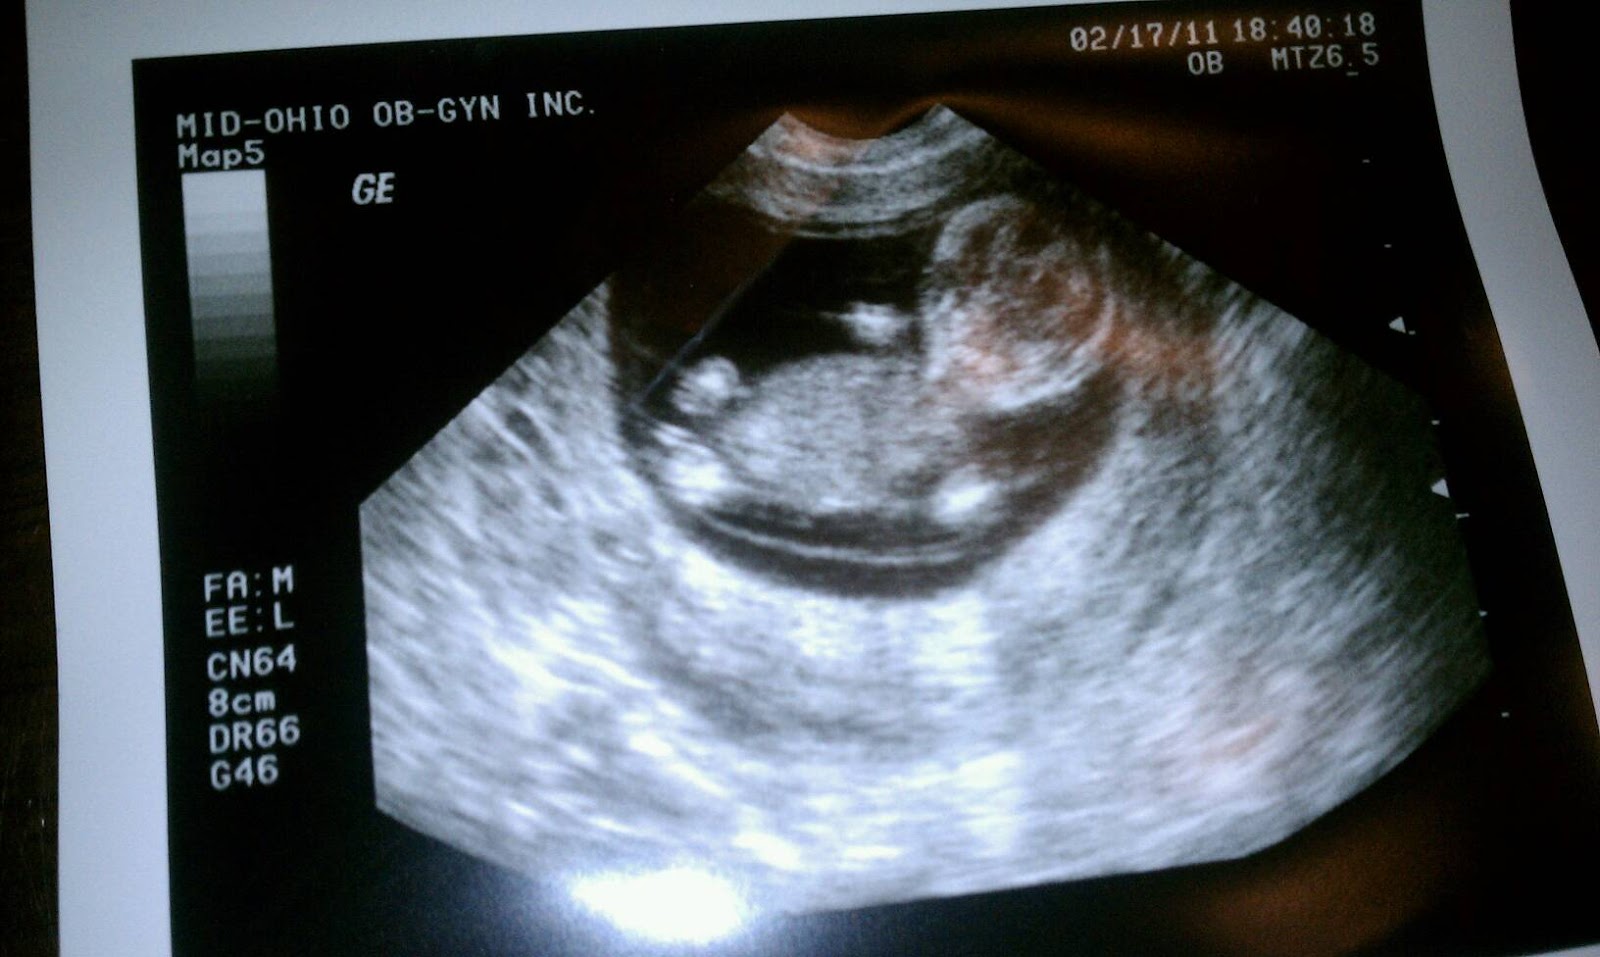

We had our second OB appt today and it was so neat! Dr. Hart asked what we thought the baby looked like last time. I said a bean. Then he showed us the baby just a few weeks later. wow. We could see the brain, hands, legs, bones... it was insane! AND he/she was moving around like crazy. It's so weird that there's all that movement and I can't feel a thing. Oh- second best part was that I only gained half a pound since last visit! Yeay me!